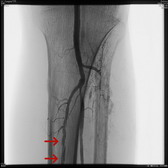

可怕的LEADDP 糖尿病下肢血管病变(LEADDP)可致患者肢体麻木、疼痛,间歇性跛行,乃至坏疽(糖尿病足),截肢率高达40 %以上。LEADDP是糖尿病致残、致死的主要原因,糖尿病患者因LEADDP造成的截肢,要比非糖尿病患者高5到10倍以上。先进的DSA + 微创介入 1、选择性血管造影(DSA)是LEADDP诊断的金标准。 2、微创介入治疗优点: 创伤小,仅有一2-3 mm的穿刺创口 成功率高:目前其成功率达85-90 % 保肢率高:术后病人截肢率可从40 %降为4 %左右 早发现早治疗:越早治疗效果越好.独创的微创介入 + HBO + bFGF综合治疗途径 1、DSA + 微创介入 2、高压氧(HBO)物理疗法:大型空气加压舱,治疗压力0.2 MPa,面罩吸纯氧30 min 3、基于重组成纤维细胞生长因子(bFGF)局部换药. |